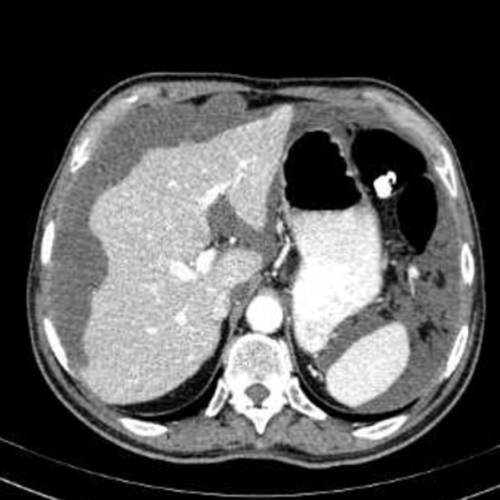

Un paziente di 50 anni si presenta con un quadro di dolore addominale, nausea e progressivo aumento di volume dell’addome. La TC addominale con contrasto mostra la presenza di una massa appendicolare. Questo è il rilievo in addome superiore.

Cosa si evince?

- Quadro normale

- Versamento periepatico

- Scalloping della superficie epatica

- Lacerazione epatica

- Versamento pleurico

Il termine scalloping (Risposta esatta: C) si riferisce a un aspetto caratteristico del fegato osservato durante l’ecografia o la TC, dove i bordi del fegato sembrano avere un profilo ondulato a causa della pressione di un processo lesivo esterno, come nel caso del pseudomyxoma peritonei. Questa condizione è una malattia rara in cui cisti di muco si accumulano nella cavità addominale, causando compressione e alterazioni morfologiche degli organi vicini, come il fegato. Il fenomeno di scalloping del fegato riflette la compressione della caps